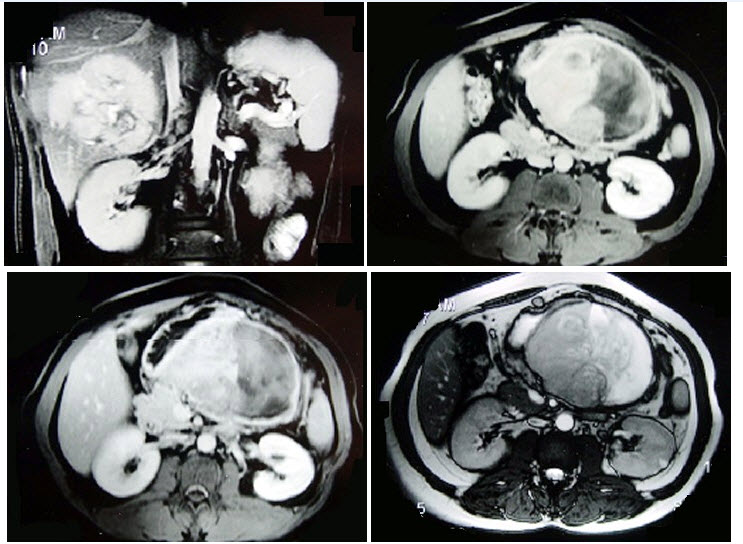

21、单项选择题

男,74岁,间歇性无痛性全程血尿2月余,尿路造影及CT平扫+增强如图所示,下列说法错误的是()

A.尿路造影示右侧肾盂内不规则的充盈缺损征象

B.CT平扫示右侧肾盂内软组织块影

C.增强扫描示右侧肾盂内软组织块影轻度强化

D.考虑为右侧肾盂癌

E.考虑为右侧肾盂内血块

40、单项选择题

男性,27岁,侏儒,因脱水曾在数家医院住过院,结合所示图像,最可能的诊断是()

A.先天性肾上腺增生肥大

B.库欣综合征

C.肾上腺癌

D.腺瘤状增生肥大

E.嗜铬细胞瘤